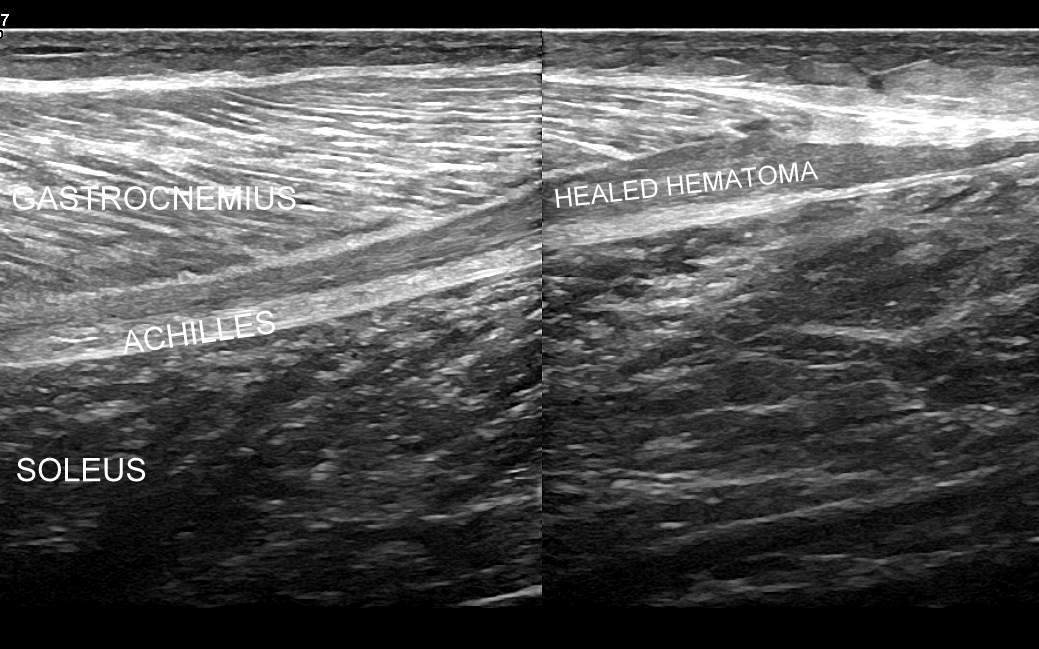

USG łydki i podudzia najczęściej służy ocenie różnorodnych urazów, których sztandarowymi przykładami są łydka tenisisty, czy naderwanie / zerwanie ścięgna Achillesa. Dr Szczepański spotyka się w swojej praktyce również z szeregiem rzadkiego typu urazów i patologii takich jak przewlekły zespół ciasnoty przedziałów powięziowych, naderwania ścięgien zginaczy, przeciążenie troczków ścięgien, shin-splint, złamania przeciążeniowe kości, malformacje naczyniowe, zmiany nowotworowe, ciała obce, czy infekcje tkanki podskórnej, powięzi, a nawet mięśni.